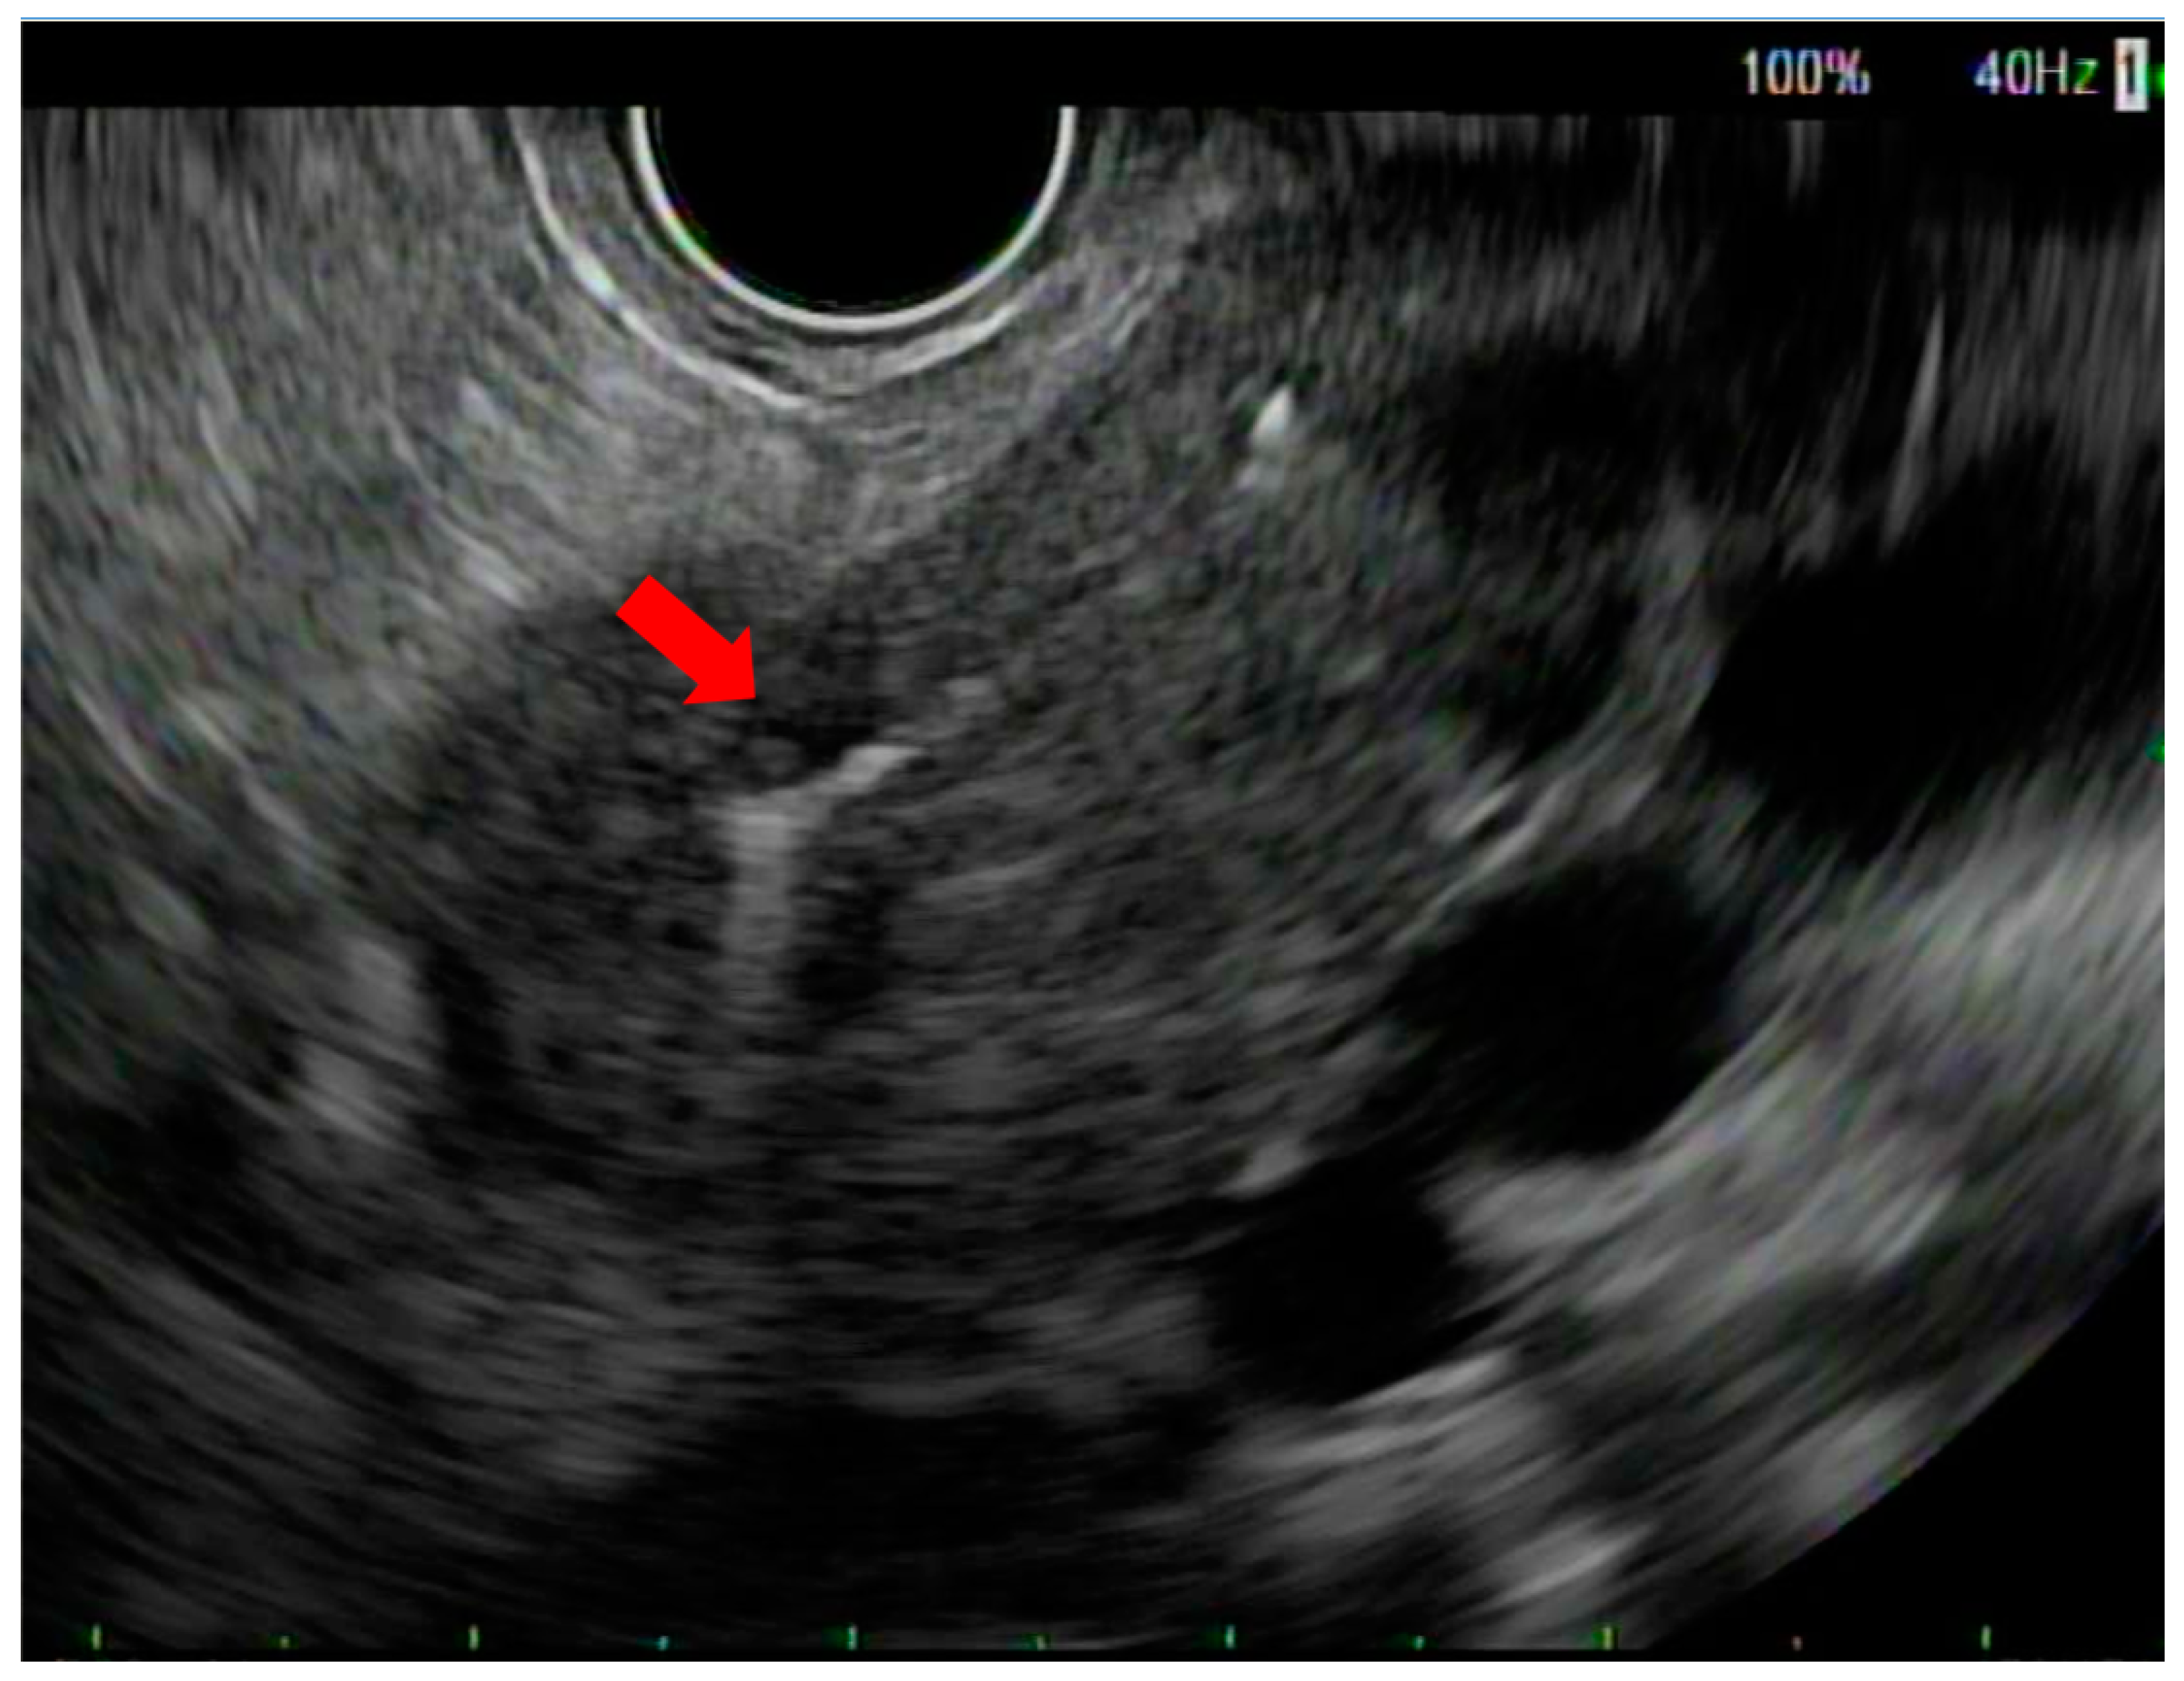

Endoscopic Ultrasound-Guided Fiducial Placement for Stereotactic Body Radiation Therapy in Patients with Pancreatic Cancer

2. Methods